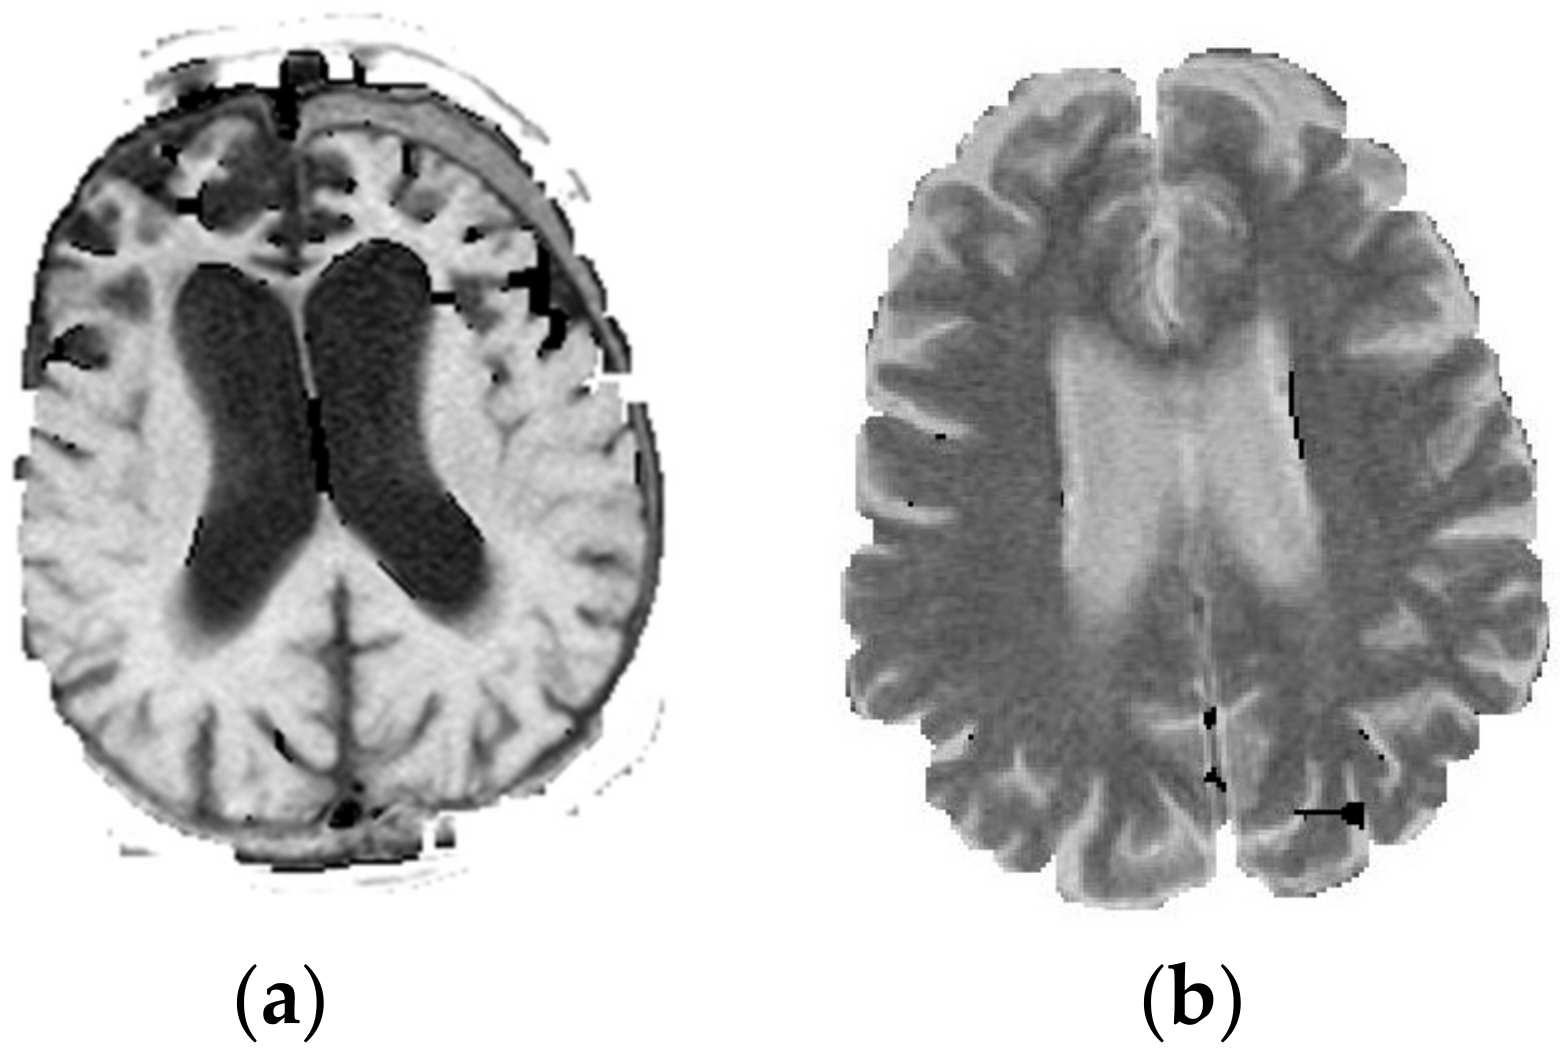

2.1. Segmentation Techniques

2.2. TV-seg Algorithm